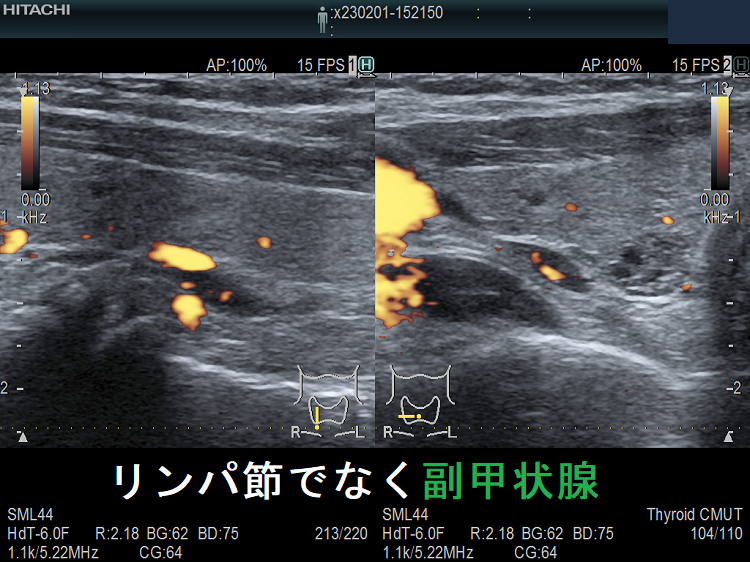

(➸)原因となる副甲状腺腺腫、副甲状腺癌、副甲状腺過形成をデジタルハイビジョン超音波診断装置で診断。エコーでは、甲状腺とのインピーダンスの違いにより、甲状腺-副甲状腺境界部に線状高エコーが生じます(右図の↓)。内部は中心血流を認め、リンパ節でないのが分かります。

副甲状腺腺腫のように見えるも、実はただのリンパ節

副甲状腺腺腫との違いとして、リンパ節では

- 内部血流が無く

- リンパ門が存在します(ここだけ血流があります)